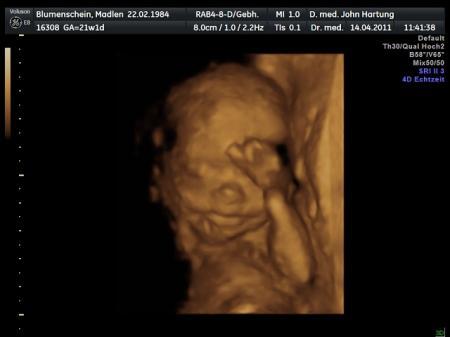

beim lachen

Bild zu